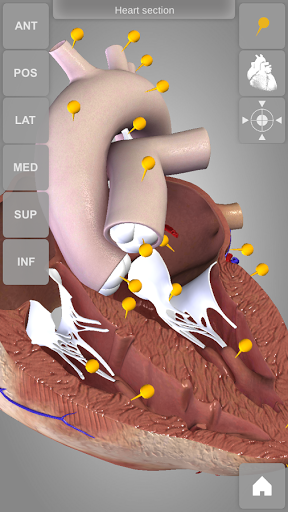

Heart 3D Atlas of Anatomy allows you to rotate a highly realistic 3D heart model as it was in your hands.

The human heart anatomical 3D model is revolvable in any direction giving a 360° view of the object.

User can choose external view or section view. Moreover, the names of specific anatomical areas can be shown touching the related pins (available in the full version only).

Heart app is part of 3D Atlas of Anatomy collection, a human anatomy reference atlas for tablet and smartphone devices. The 3D medical models in these apps are similar to classic real plastic models but with the great benefits to be always available on your portable devices when you need them and occupy no physical space.

These apps can be of great help for students of medicine or to anyone who needs to study human anatomy shape in detail and from any angle. Immediacy and simplicity together with high quality are distinctive features of the app.